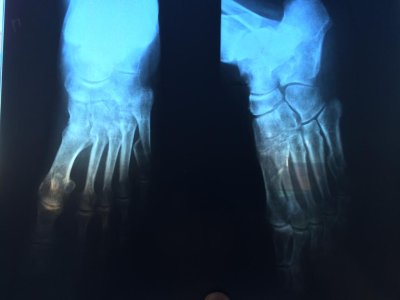

10 марта мама ( 60 лет) сломала 5 плюсневую кость, прилагаю первый снимок и последний, сделанный 30 апреля. Как на ваш взгляд проходит срастание кости? как долго еще носить гипс? можно ли сейчас наступать на ногу?

учитывая массу тела серьезных проблем возникнуть не должно.На первичном рентгеновском снимке есть все показания для оперативного лечения.

Еще раз говорю на снимках очень плохо видно,но кажется начинает формироваться периостальная костная мозоль.Нужно смотреть функцию конечности.Возможно для большего удобства заменить гипс на ортез